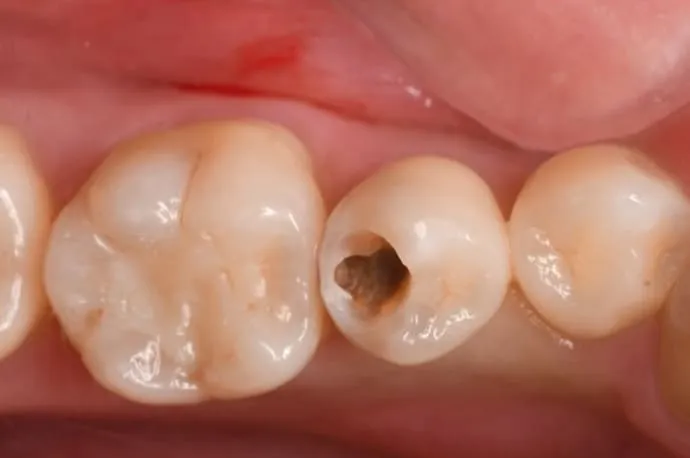

• 歯に黒ずみや穴がある

一見すると穴が空いていないように見えますが、内部で虫歯が広がっている状態です。

STEP 02

歯の表層を削ると、中は大きな空洞になっています。